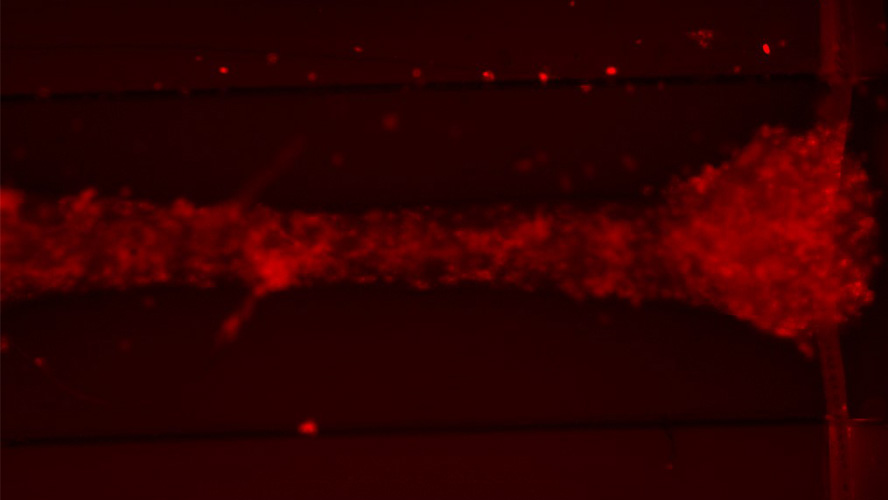

Image of cardiac tissue formed using human embryonic stem cell-derived cardiomyocytes, fibroblasts, and macrophages. Red staining shows the stem cell derived-macrophages.

“Using a previously established system, we generated 3D contractile cardiac tissue composed of stem cell-derived cardiomyocytes and fibroblasts that stably integrate with stem cell-derived macrophages (hESC-macrophages),” says Homaira Hamidzada, a doctoral candidate in Dr. Epelman’s lab and first author of the study.